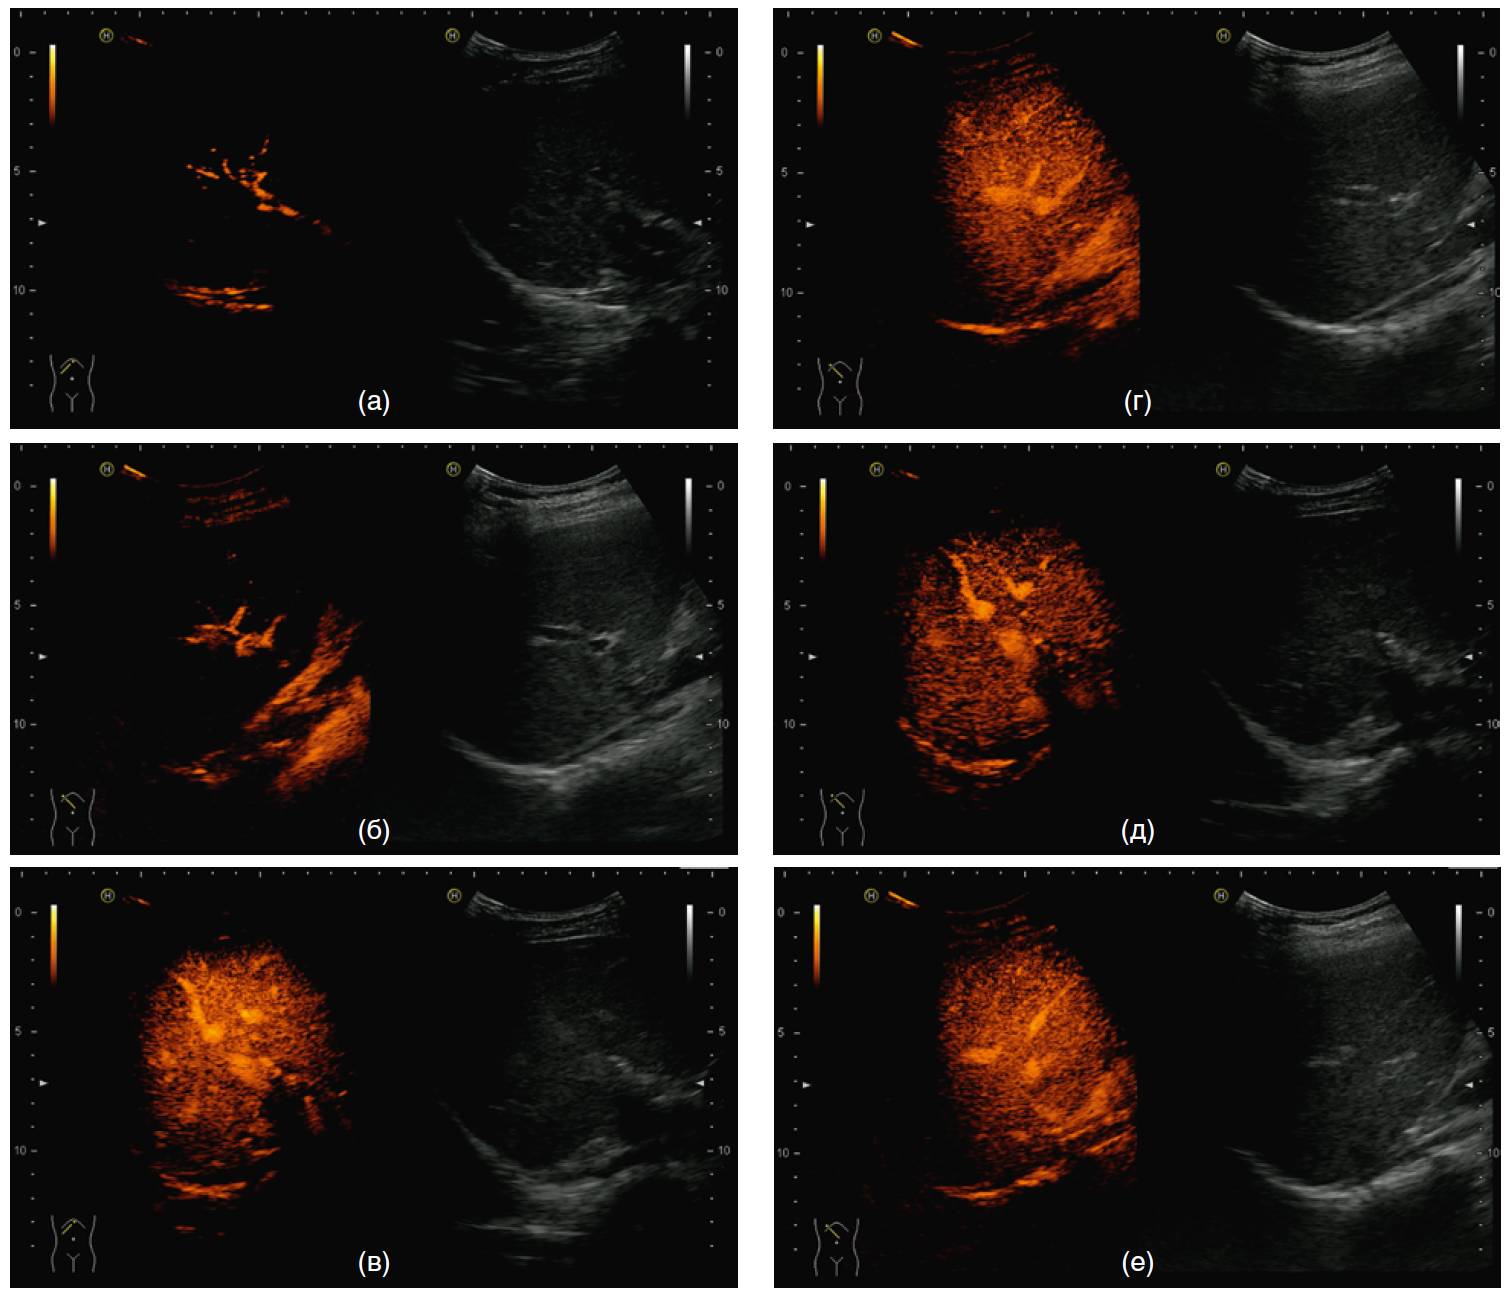

Качественные показатели КУУЗИ у пациентов различных групп (2,5 и 1,0 мл контрастного препарата) отражены на рис. 2, 3, при этом качество изображений, полученных при введении 1,0 мл контрастного препарата, было идентично или несколько ниже, чем при введении 2,5 мл, но достаточным для оценки.

Рис. 3. Качественная оценка контрастно-усиленного ультразвукового исследования печени при введении 2,5 и 1,0 мл контрастного препарата: выявлены деформация сегментарных и внутрисегментарных артерий, зоны неоднородного вымывания контрастного препарата в портальной и поздней венозной фазах (S VIII–VII–VI–V)

Примечание. а — артериальная фаза, 2,5 мл; б — артериальная фаза, 1,0 мл; в — портальная фаза, 2,5 мл; г — портальная фаза, 1,0 мл; д — поздняя венозная фаза, 2,5 мл; е — поздняя венозная фаза, 1,0 мл.